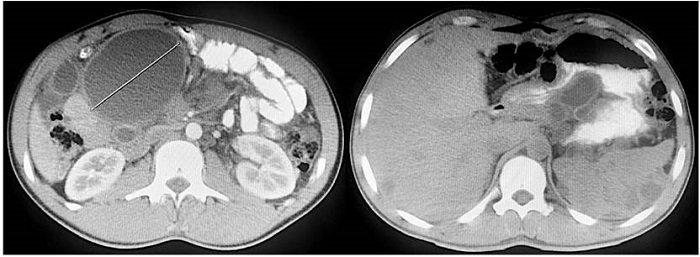

Se le realizó una tomografía de abdomen y pelvis simple y contrastada, donde se documentó hepatoesplenomegalia leve, quistes simples intrahepáticos y esplénicos de distribución difusa, quistes mesentéricos, también en forma difusa, dilatación de asas intestinales con importante distensión del duodeno (Figura 2). Se valoró en junta quirúrgica de Cirugía General, donde se consideró que, por hallazgos en estudios imagenológicos, con etiología no clara, se debía descartar colecciones residuales de procedimientos quirúrgicos previos y se debía llevar a laparotomía exploratoria, con resección de quistes para realizar y estudio patológico para definir la etiología y conducta final.